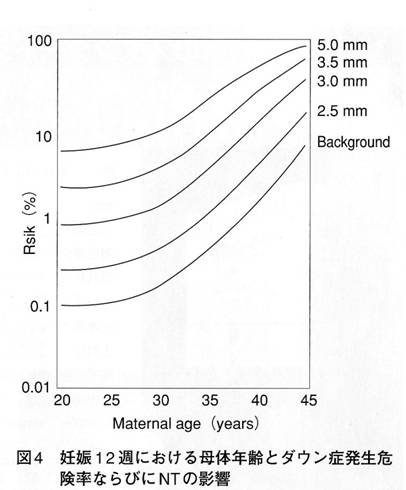

先天異常部より Nt Nuchal Translucency について 医療者向け 日本産婦人科医会

14 初期の超音波マーカー検査 日本産婦人科医会

先天異常部より Nt Nuchal Translucency について 医療者向け 日本産婦人科医会

妊娠初期超音波の出生前診断における役割 Fetal Skeletal Dysplasia Forum

胎児超音波ーマーカー検査とは ヒロクリニック

妊娠初期超音波の出生前診断における役割 Fetal Skeletal Dysplasia Forum

ダウン症nt検査とは何の事なのか ダウン症についてしっかり知ろう ダウン症の原因は